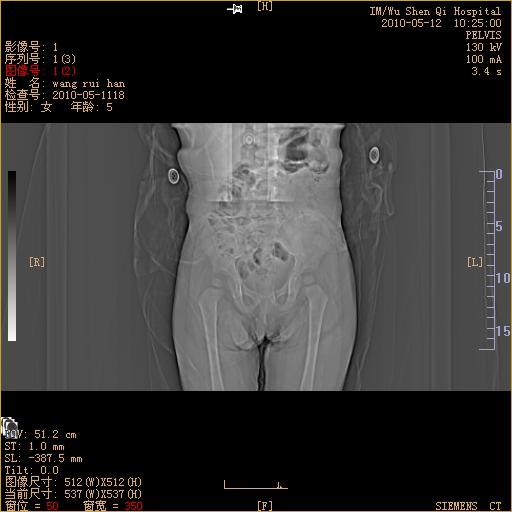

标题: PED3243:1周半,右髋部疼痛伴下肢活动受限,帮忙看看是否

定位像是否感觉右侧间隙增宽?

右侧髋关节间隙内有积液。请结合临床。

右侧滑囊积液。

右髋关节间隙增宽 右股骨头稍向外上移不排除半脱位

从定位片上看,右股骨头骨骺位于帕金氏方格中心处,结合临床,应考虑有脱位的存在.

右髋关节间隙较对侧大,有股骨头略想外上方移位,申通氏线不连续。

考虑右髋关节脱位可能。